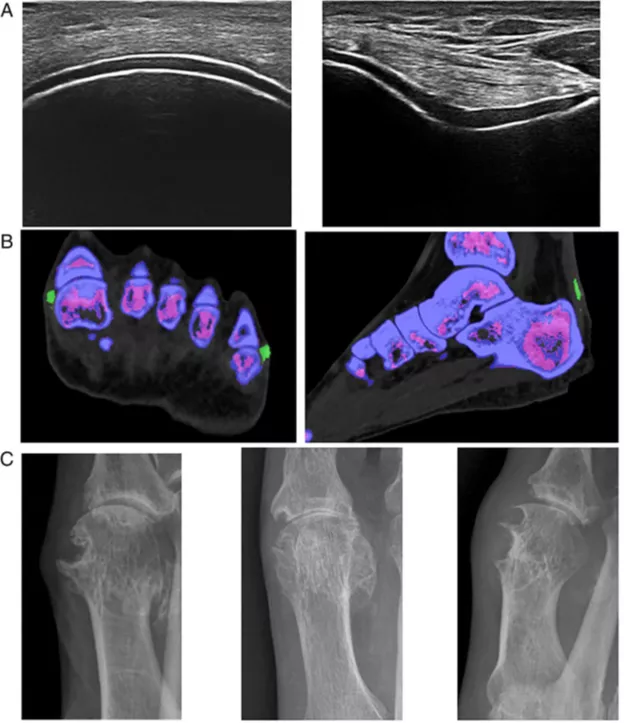

Признак «двойного контура» - наличие поверхностного гиперэхогенногослоя (отложение моноурата натрия) на поверхности хряща (фото 16А) входит в критерии подагры ACR/EULAR 2015 (см. ниже). Характерен вид «метели» в синовиальной жидкости. Тофусы выглядят негомогенными образованиями с анэхогенным ободком. Причем тофусы могут выявляться до клинической манифестации артрита

Двухэнергетическая компьютерная томография (ДЭКТ) специфична для обнаружения отложений кристаллов уратов и их дифференцировки с отложениями кальция [16]. Обнаружение уратов при помощи ДЭКТ (фото 16B) входит в критерии подагры ACR/EULAR 2015 (см. ниже)

Фото 16 А,B,С [12]:

А – Симптом двойного контура на УЗИ. Левое фото показывает продольное ультразвуковое изображение бедренного суставного хряща; на правом фото показано поперечное ультразвуковое изображение бедренного суставного хряща. На обоих изображениях видно гиперэхогенное усиление на поверхности гиалинового хряща.

B - Отложение уратов на двухэнергетической КТ. На левой панели показано отложение уратов в первом и пятом плюснефаланговых суставах; на правой панели показано отложение уратов в ахилловом сухожилии (отложения уратов маркируются зелёным цветом)

C - Эрозия, определяемая как кортикальный разрыв со склеротическим краем и нависающим краем, видимая на обычной рентгенографии первого плюснефалангового сустава.

* Гиперэхогенное неравномерное усиление над поверхностью гиалинового хряща, не зависящее от угла ультразвукового луча (ложноположительный признак двойного контура исчезает при изменения угла) – см. фото 16А

** Наличие уратов с цветовой кодировкой в суставных или периартикулярных зонах. Изображения должны быть получены с использованием ДЭКТ при 80 кВ и 140 кВ, и проанализированы с использованием специальной программы (2-material decomposition algorithm), которая кодирует ураты цветом. Положительный результат сканирования определяется как наличие уратов с цветовой кодировкой в суставных или периартикулярных участках – см. фото 16B

*** Эрозия определяется как кортикальный разрыв со склеротическим краем и нависающим краем, (исключая дистальные межфаланговые суставы и симптом «крыльев чайки») – см. фото 16C